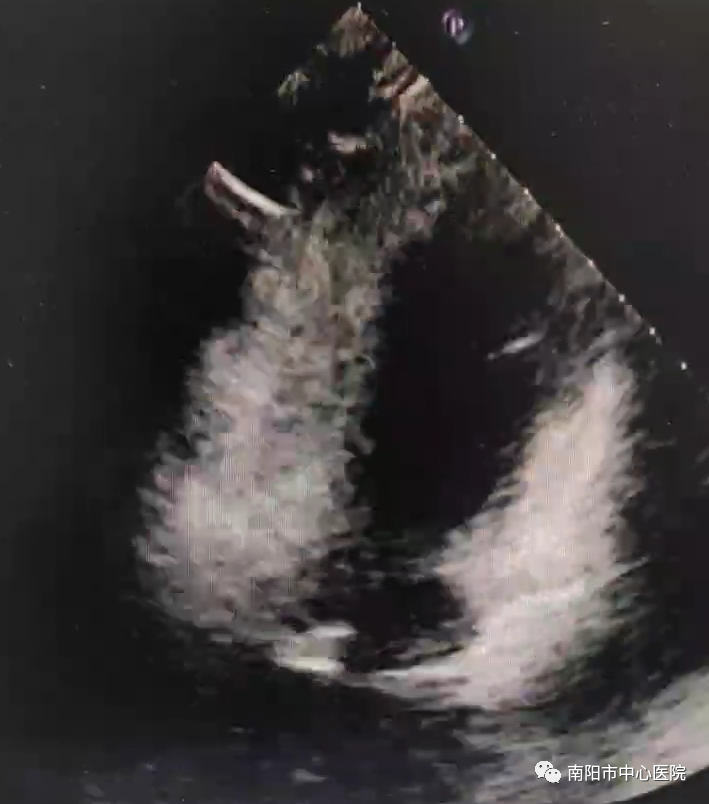

為了印證微氣泡分流來源于卵圓孔,又給患者做了經(jīng)食管超聲心動(dòng)圖聲學(xué)造影(cTee),可以清楚看到微氣泡經(jīng)卵圓孔位置分流入左房,診斷明確。